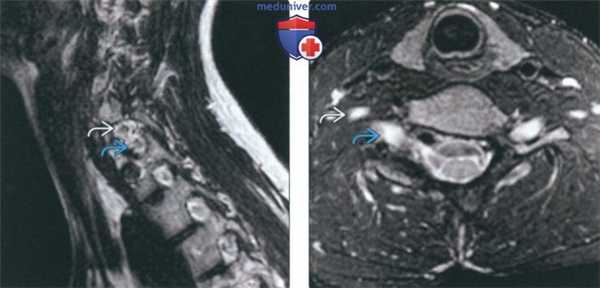

(Слева) На фронтальном Т1-ВИ (миеломенингоцеле, сколиоз) определяется правосторонняя сколиотическая деформация грудного отдела позвоночника с множественными аномалиями формирования позвонков в средне- и нижнегрудном отделе. У этого пациента также обнаружена диастематомиелия (не показана).

(Справа) На аксиальном Т2-ВИ (миеломенингоцеле, диастематомиелия) на уровне Т10 виден причудливой формы аномально расширенный позвонок, представляющий собой «позвонок-бабочку» с патологически измененным межпозвонковым диском. Обратите также внимание на сирингомиелию правой половинки спинного мозга.

(Слева) На сагиттальной МРТ (Т2 ВИ) определяется расширение правою межпозвонкового отверстия С6-С7 по сравнению с нормальными отверстиями выше и ниже этого уровня. Правое межпозвонковое отверстие С6-С7 более чем в два раза шире, чем левое (не показано) на этом уровне. Обратите внимание на два нерва, проходящих через расширенное отверстие.

(Справа) На аксиальной МРТ (Т2 ВИ) определяется расширение правого межпозвонкового отверстия С6-С7, в котором проходят сразу два нерва, а не один.